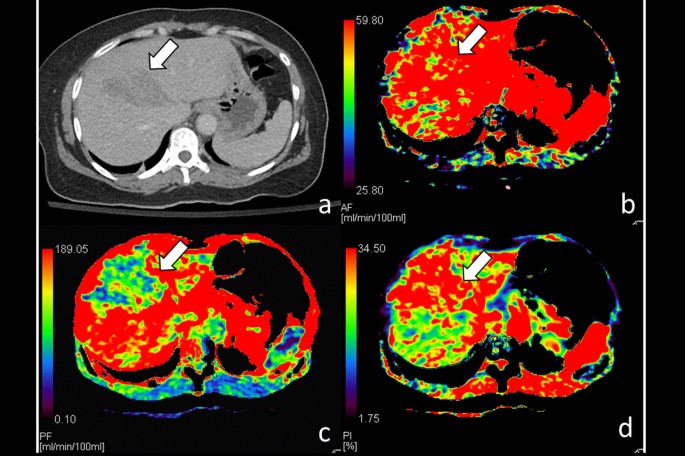

CT of a 34-year-old woman with grade IV liver injury at right lobe after embolization management. (a) Contrast-enhanced CT of the liver shows extensive right lobe injury (arrows); (b) hepatic arterial perfusion CT and (c) hepatic portal venous perfusion CT show decreased arterial and portal venous flows to traumatic parenchyma at right lobe (arrows); (d) hepatic perfusion index which is a ratio of arterial perfusion to the total hepatic perfusion is normal at traumatic parenchyma (arrows).

Liver CTP examinations of all patients were performed on a mean of 9.6 ± 3.6 days after blunt liver trauma and successfully treated with NOM. The mean radiation dose of liver CTP was 12.0 ± 2.5 millisievert. Among 9 patients of embolization group, their whole liver hepatic arterial perfusion (HAP) 78.1 ± 69.3 versus 163.1 ± 134.3 mL/min/100 mL, p = 0.011, and portal venous perfusion (PVP) 74.4 ± 53.0 versus 160.9 ± 140.8 mL/min/100 mL, p = 0.008 were significantly lower at traumatic parenchyma than at non-traumatic parenchyma (Table 2). However, the difference of whole liver hepatic perfusion index (HPI) between trauma and non-traumatic parenchyma did not differ (Fig. 2).